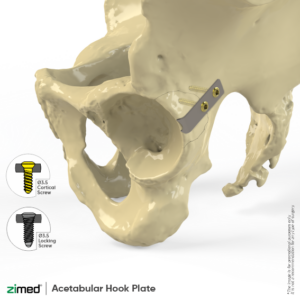

Acetabular Hook Plates